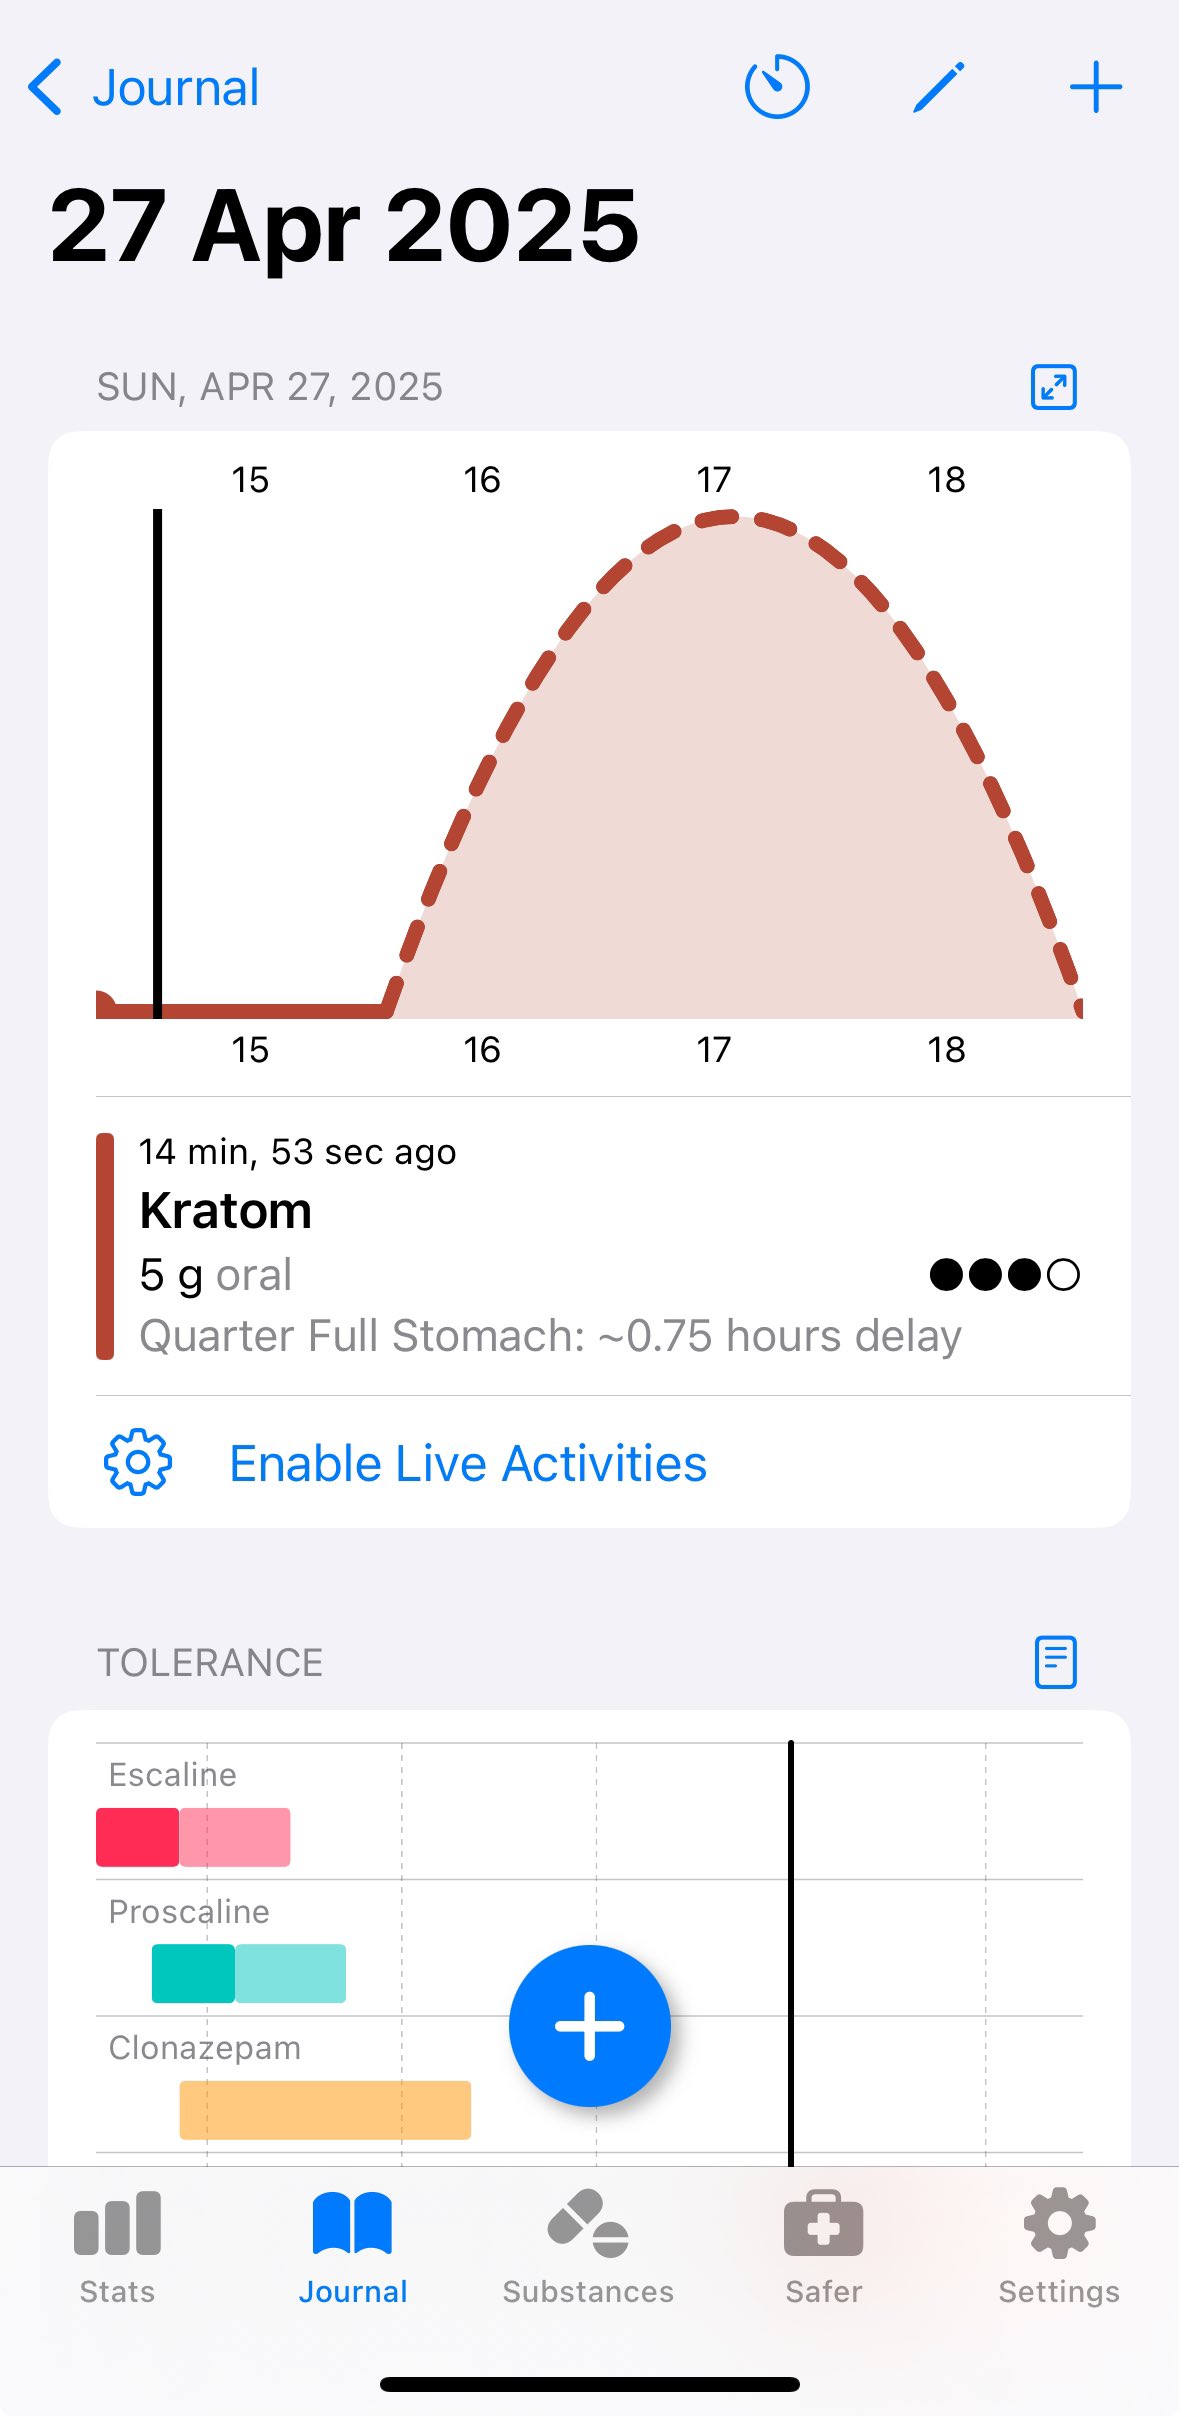

炽烈已极 @AnIncandescence@whitenightX3 journal